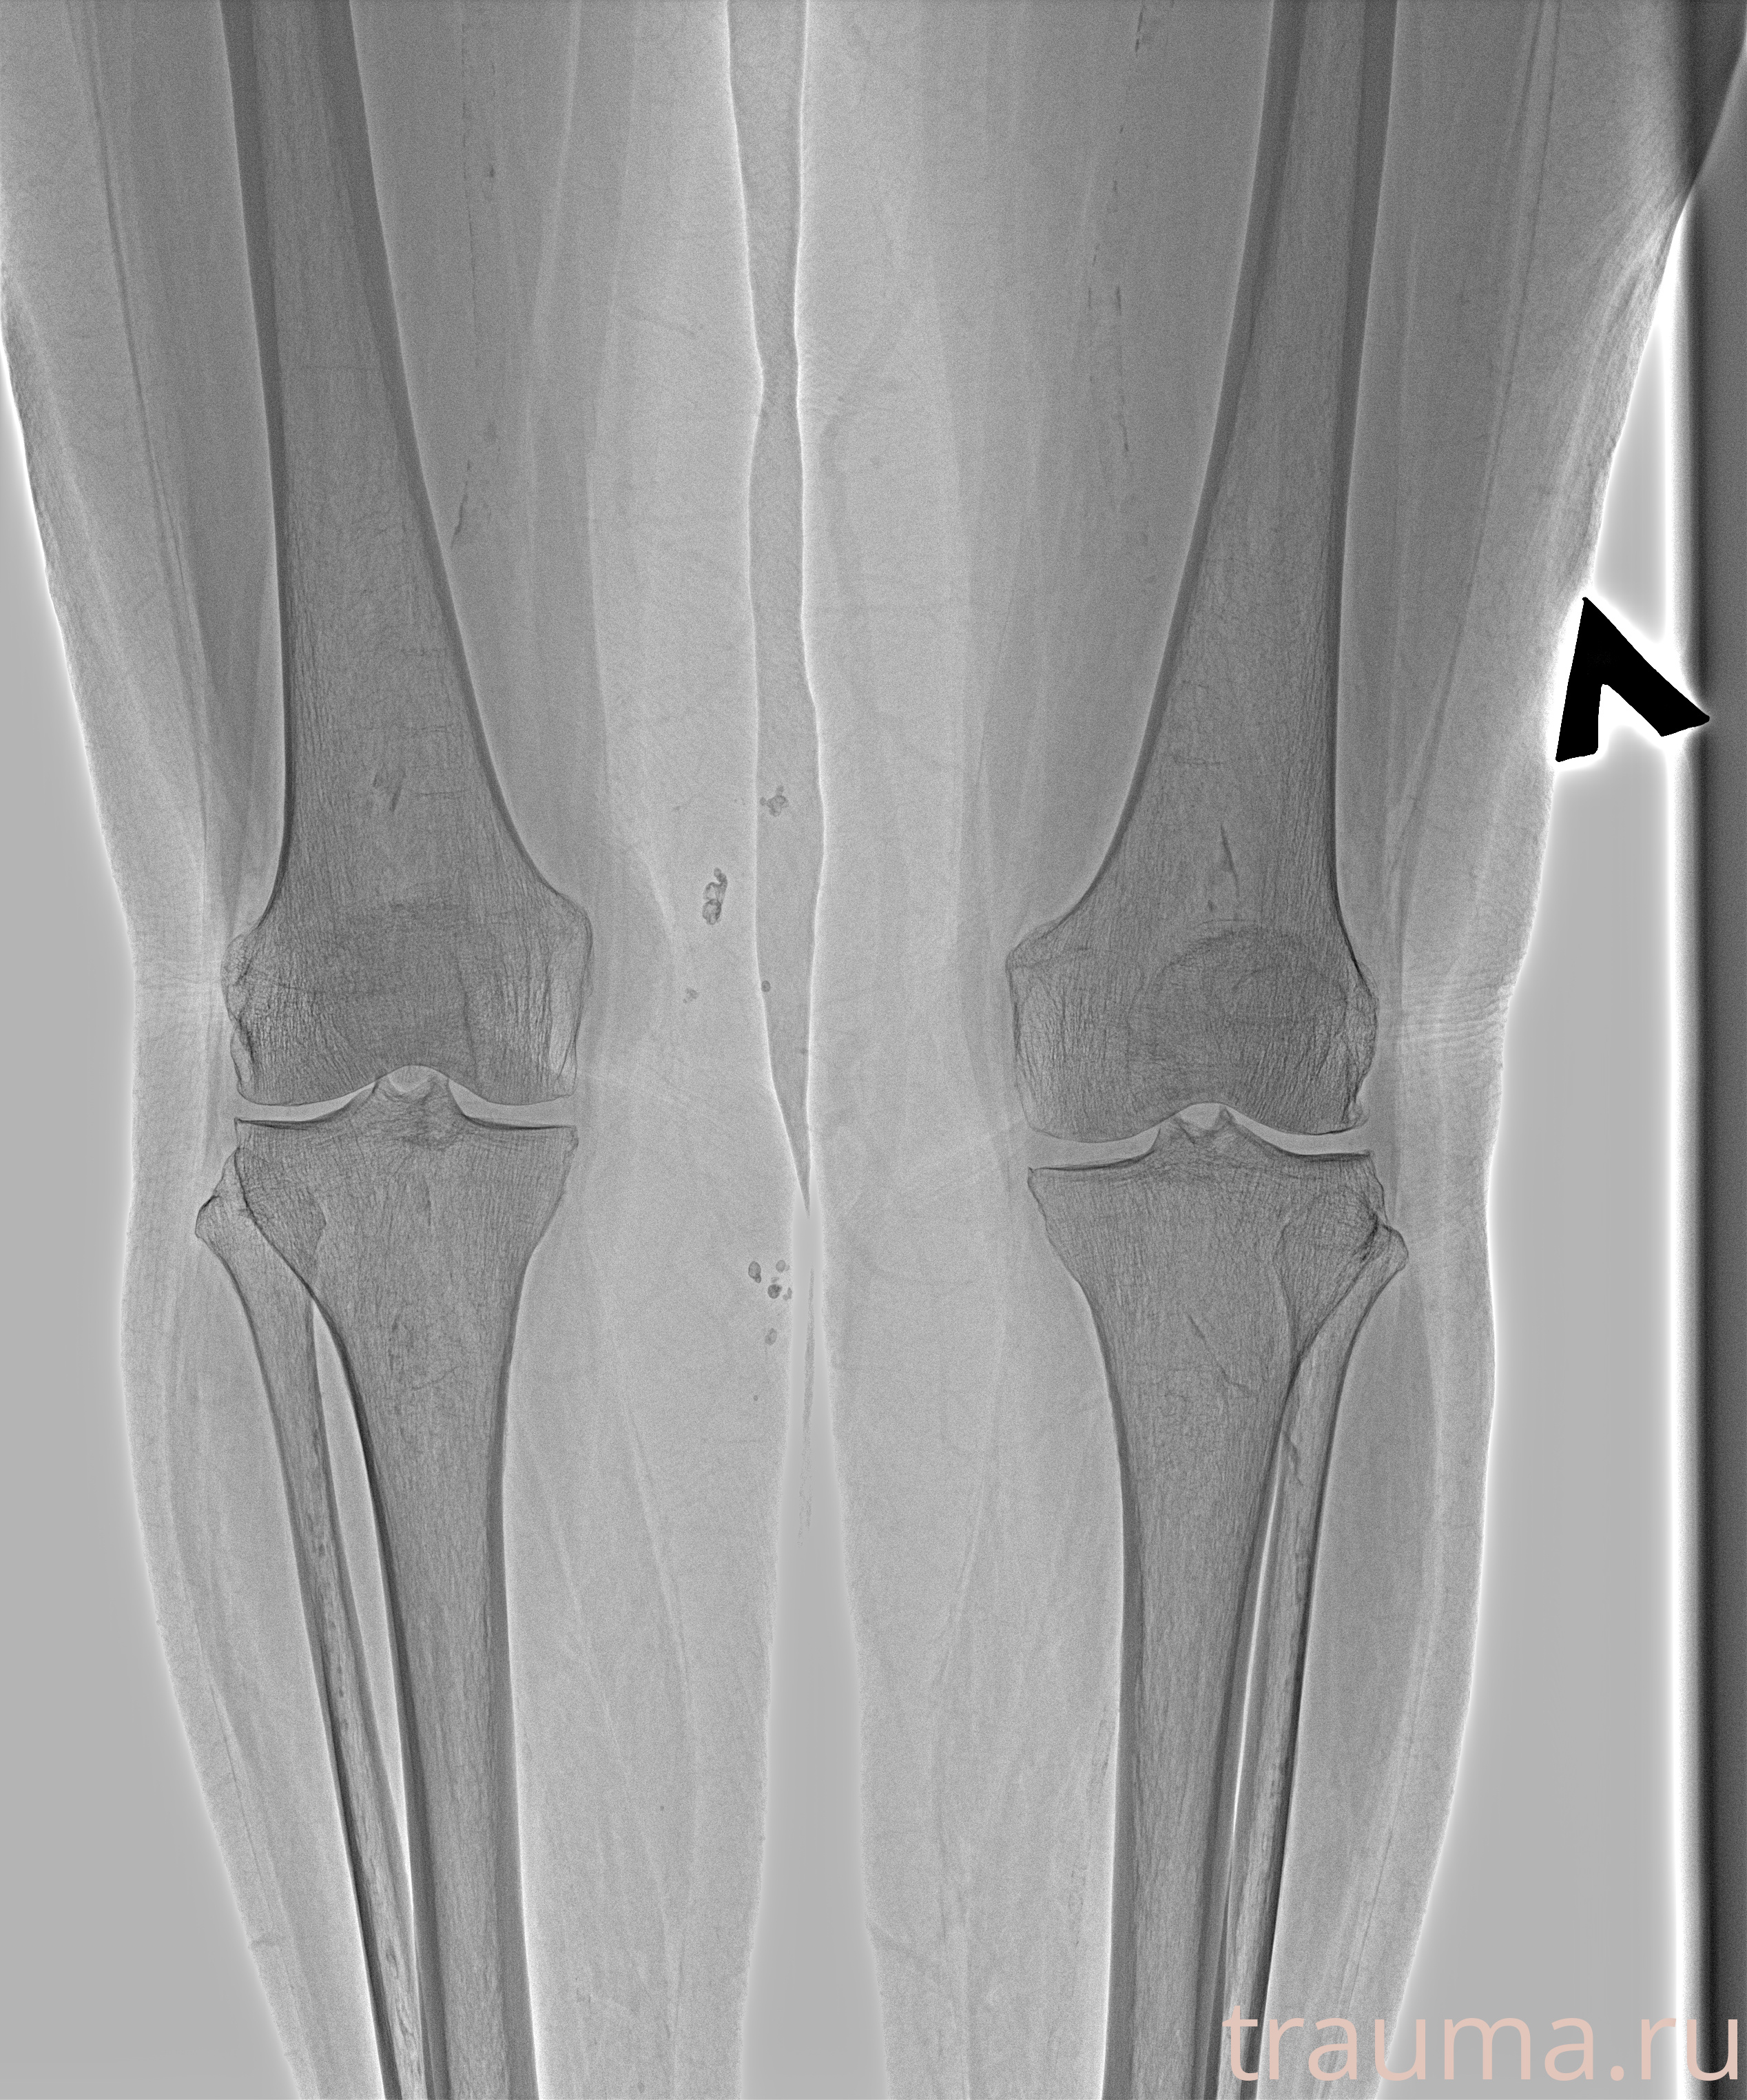

Рентгенограммы

Рентген на дому: по вашему адресу приезжает врач-рентгенолог, травматолог-ортопед с мобильным рентгеновским аппаратом, проводит диагностику травмы или заболевания, делает необходимые рентгенограммы, дает рекомендации по дальнейшему лечению. Получить качественные снимки в домашних условиях возможно благодаря уникальной методике, разработанной МосРентген Центром для института  Склифосовского